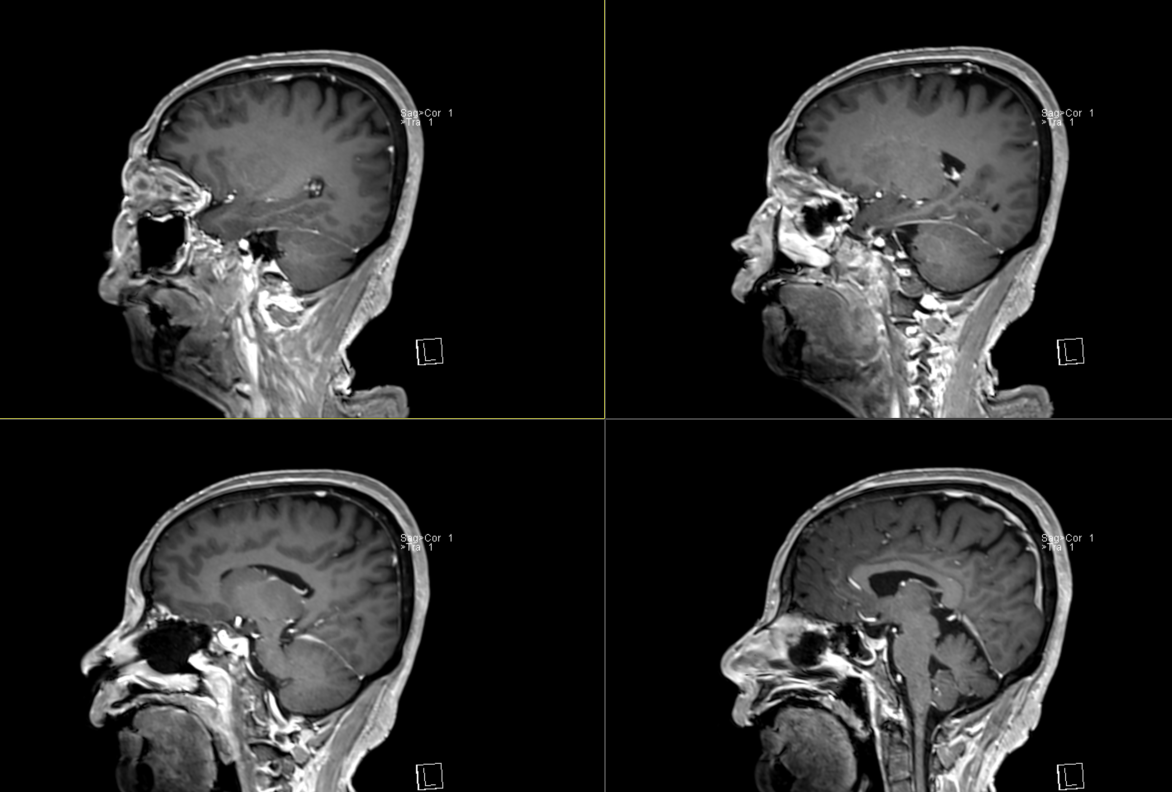

术前影像:

术前影像: